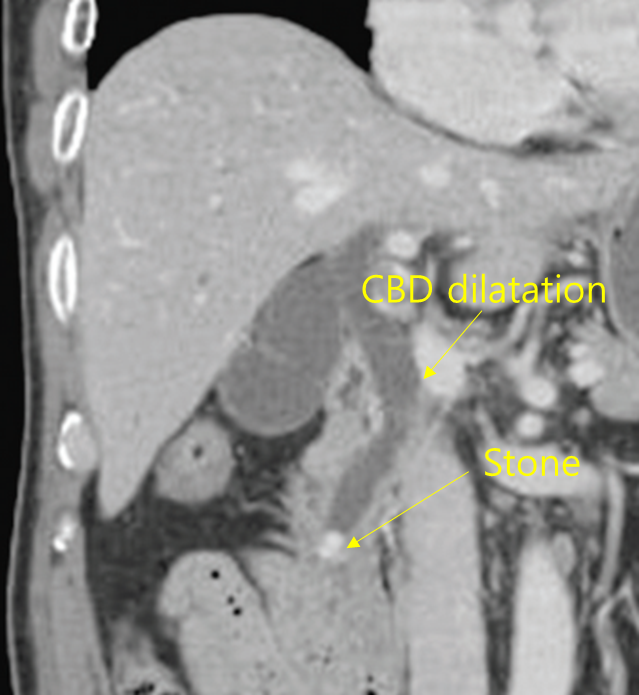

Img | CT: 담관내 결석, 담관 확장 |

식후에 심해지는 우상복부 통증을 주소로 내원한 환자로, 발열, 황달이 동반되어 있어 급성 담관염이 의심된다. 혈액검사에서도 총빌리루빈, ALP/GGT 상승 등 담즙정체 소견이 확인되며, 결정적으로 CT에서 담관 내에 하얀 결석과 이로 인한 담관 확장이 관찰되므로 급성 담관염으로 진단할 수 있다. Ampula of vater 부근에서 폐쇄가 발생하여 amylase, lipase도 상승한 것으로 보인다. 담석에 의한 급성 담관염은 ERCP를 통한 오디조임근절개술(sphincterotomy, EST)을 시행하여 stone removal을 하여야 한다.

진단 | • US/CT: Bile duct dilatation, stone이 보일 수도 있음 • MRCP/ERCP: Proximal bile duct dilatation, filling defect 등 |